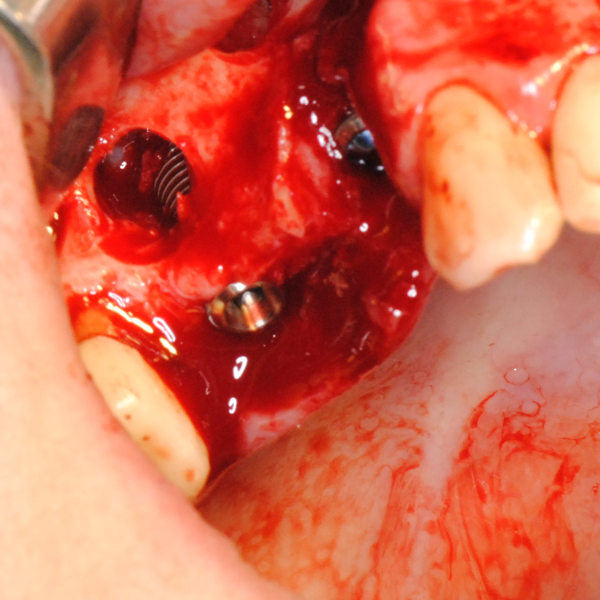

Схема на открития синуслифтинг

Видеоклип за открит синуслифтинг Пластинка Сasios